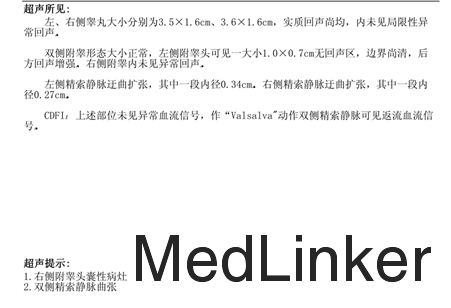

体格检查:T36.4 ℃ P84 bpm R 20次/分 BP 126/71mmHg 肛门外生殖器无畸形,双侧精索静脉曲张。 辅助检查: 2015-07-13在同济医院行性激素检查无异常;彩超检查双侧精索静脉曲张;2015-06-22、2015-07-13精子质量分析均较差;2015-08-06、2015-0909精子质量分析未见精子;2015-09-29精浆分析无异常。